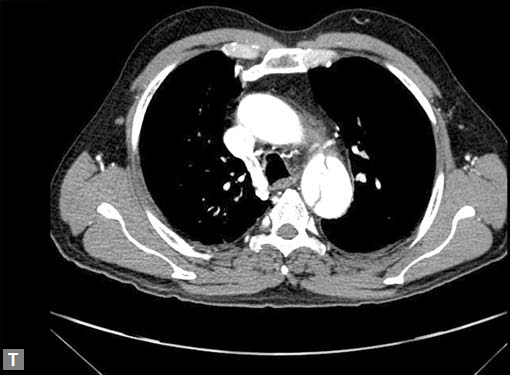

Connective tissue disease, hypertension and iatrogenic (Figs 19K to L) injury are the common causes for dissection. Radiologist not only establishes the diagnosis, also evaluates the extent of dissection, presence of thrombosis particularly in false lumen. In case of type A dissection, involvement of aortic root is determined. Relation of thrombosed lumen and ostia of coronary vessels, cephalad branches (Figs 19N, R to V) of aorta is determined. Most of the occasions membrane is demonstrated. Spiral nature of the membrane can be seen

by evaluating the aorta in all the three orthogonal planes

(Figs 19O to R).

Tennis ball sign is the classical appearance of dissection on

transverse section.

Double barrel appearance is seen on coronal and sagittal

images. Type B dissections can extend even to common

iliac arteries bilaterally. Superiorly it can extend to involve

common carotid and vertebral arteries.

Second dissection within the true lumen causes “Benz”

sign (Fig. 19J).

Figs 19A to Y (A to C) Scannogram (A), plain (B) and contrast study (C) show partial anomalous pulmonary venous connection; (D to F) Heterotaxy; (G) Aortic occlusion; (H and I) Aortic stents; (J) Aortic dissection with ‘Benz’ sign due to second dissection within the true lumen; (K, L and M) Aortic dissection with thrombus in pseudolumen following catheter angiogram; (N) Aortic dissection involving common carotid arteries and subclavian artery; (O, P, Q and R) Aortic dissection with right renal artery arising from true lumen and left renal artery from false lumen; (S, T, U and V) Stanford B dissection with extension Y to iliac vessels; (W to Y) Aneurysmal dilation of ascending aorta